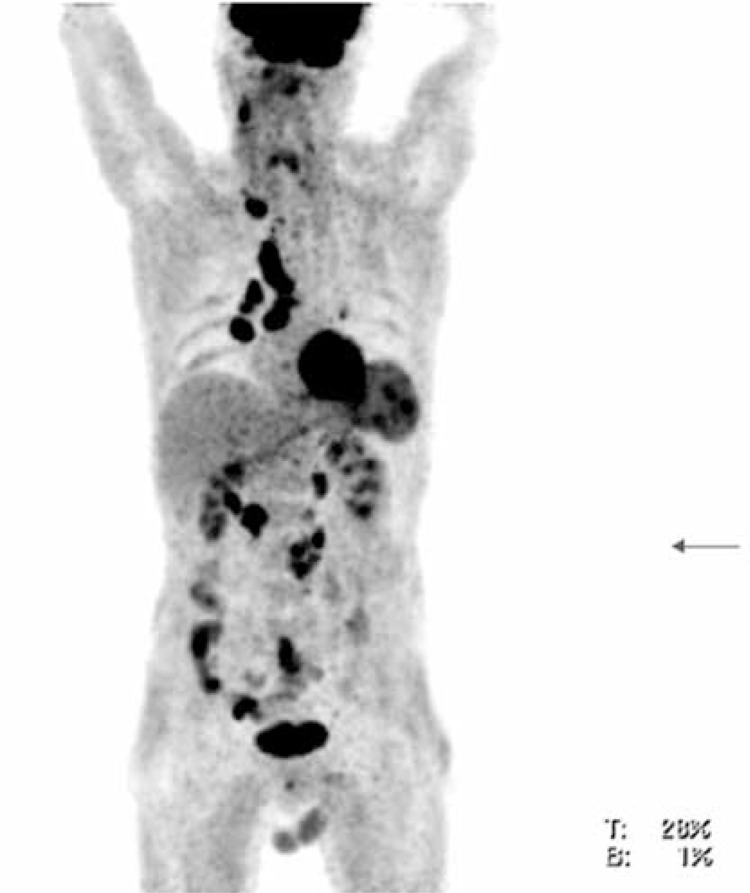

18F-FDG PET/CT findings were true positive in 69 (76.7%) patients (Figure 2), true negative in 10 (11.1%), false positive in 5 (5.5%), false negative in 6 (6.7%). The mean SUVmax value was 6.8 +6.2. Diagnostic sensitivity of 18F-FDG PET/CT was 92.0%, specificity 66.7% and accuracy 87.8% (Table II).

Figure 2.

18F-FDG PET/CT maximal intensity projection (MIP) in the anterior view from the base of the skull to the mid thighs of the same patient with thyroid medullary carcinoma. Increased metabolism can be seen in neck, mediastinal, hilar and retroperitoneal lymph nodes, left lobe of the thyroid, spleen and colon